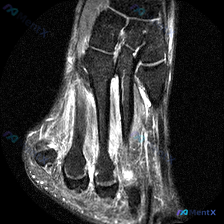

刚整理完一份踝关节MRI T2轴位影像的分析资料,这个病例其实挺有代表性的——只有少量局限性积液,其他结构都没明显异常,很多时候临床解读很容易出现过度诊断或者漏诊,分享一下我的分析思路。 一、影像基本信息 这是踝关节水平的轴位T2扫描,先给大家整理所有观察到的信息: 1. 骨骼结构:胫骨远端、距骨髓...